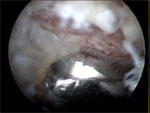

διαμέσου οπτικών ινών. Το αρθρωσκόπιο στο άκρο του φέρει πολύ

μικρού μεγέθους κάμερα η οποία είναι συνδεδεμένη με μια οθόνη

όπου απεικονίζεται το εσωτερικό της άρθρωσης. Με αυτή τη μέθοδο